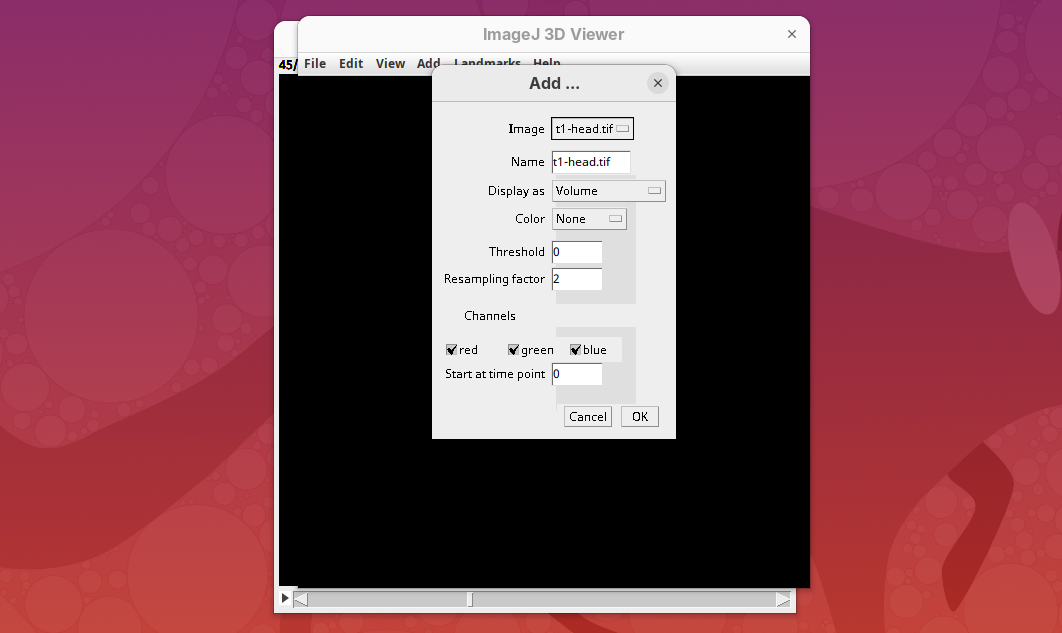

- Go to

Plugins>3D Viewer.

An import dialog will open. In addition to the image field itself, pay attention to the Resampling factor parameter. The default is 2, which means 2x downsampling of the original stack. Always downsample at least 2x because 3D Viewer will crash when trying to open large datasets.

- Click

OKon the options dialog and when asked about converting to 8-bit.

The main interface will open.

- Explore the sample interactively.